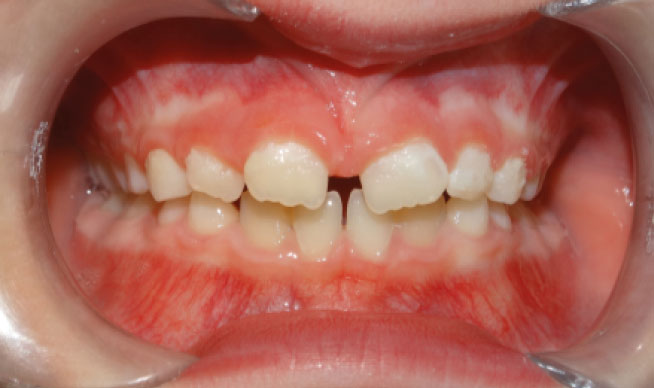

la présence d’une supraclusion, cela signifie que le recouvrement des incisives inférieurs par les incisives supérieures est trop important. Autrement dites, les dents du dessus « cachent » celles du bas, c’est pourquoi on parle aussi de recouvrement dentaire. La supraclusion se manifeste par un recouvrement trop important des incisives inférieurs par les incisives supérieures. Les dents du dessus « cachent »les dents du bas. Ce trouble est fréquent et est aisément traitable grâces aux nouvelles techniques d’orthodontie. Grâce aux nouvelles techniques d’orthodontie, le traitement est facilité́. Il n’est plus nécessaire de porter des « casques » externes et il est très rare d’extraire des dents. Le port de rackets (les « bagues ») permet de résoudre le problème chez l’enfant et l’adulte.